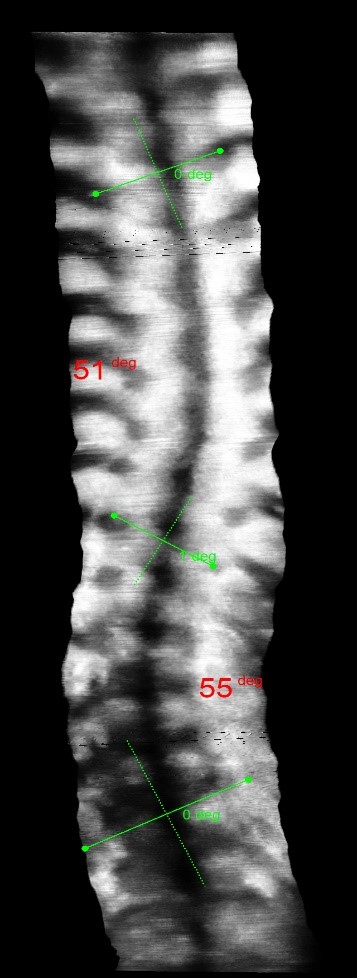

The clinical test results show that the SCN800 series is highly consistent with the X-ray, with a linear correlation of 0.94, similar results have also been published in SCI articles (Lee TT, Lai KK, Cheng JC, Castelein RM, Lam TP, Zheng YP. 3D ultrasound imaging provides reliable angle measurement with validity comparable to X-ray in patients with adolescent idiopathic scoliosis. Journal of Orthopaedic Translation. 29:51-59, 2021).

In our clinical trials and studies, we measured two angles to facilitate comparison. X-rays can actually show 3 to 4 angles, some in the neck and bottom area. Ultrasound images can also measure angles near the neck like an X-ray.

The following images compare 5 ultrasound and X-ray clinical measurement examples: